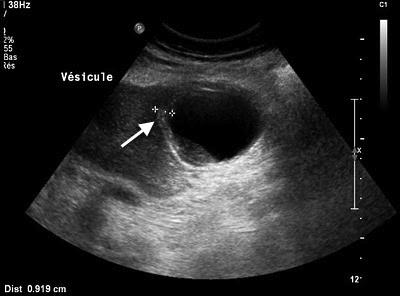

L’échographie est l'examen d’imagerie de première intention pour le diagnostic de cholécystite aiguë lithiasique. Les signes sont un épaississement de la paroi vésiculaire (> 4 mm), la présence d’un liquide péri-vésiculaire, une douleur au passage de la sonde sur l’aire vésiculaire (réalisant le signe de Murphy radiologique) et bien sur une image de calcul intravésiculaire.

Figure n°1 : Cholécystite aiguë à l'échographie.

(Flèche : paroi vésiculaire épaissie)